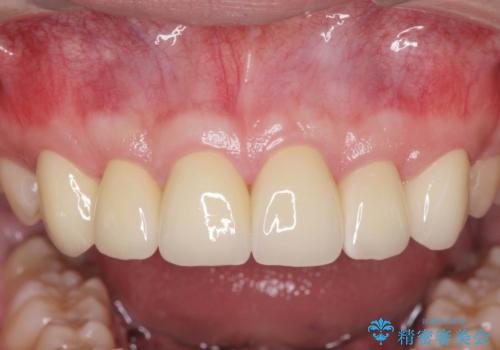

歯周外科を行い、歯ぐきの状態を整えた前歯セラミック治療

- 「前歯の見た目、歯ぐきの腫れを改善したい。」と希望され来院されました。

前歯には接着性の維持装置や、中途半端な形の連結クラウンが装着され、清掃性が悪く歯ぐきの腫れや、歯ぐきの形態の不揃いが認められました。

歯周外科を行ったことで、歯ぐきの形態や腫れが改善され、審美性だけでなく清掃性も大きく改善することができました。